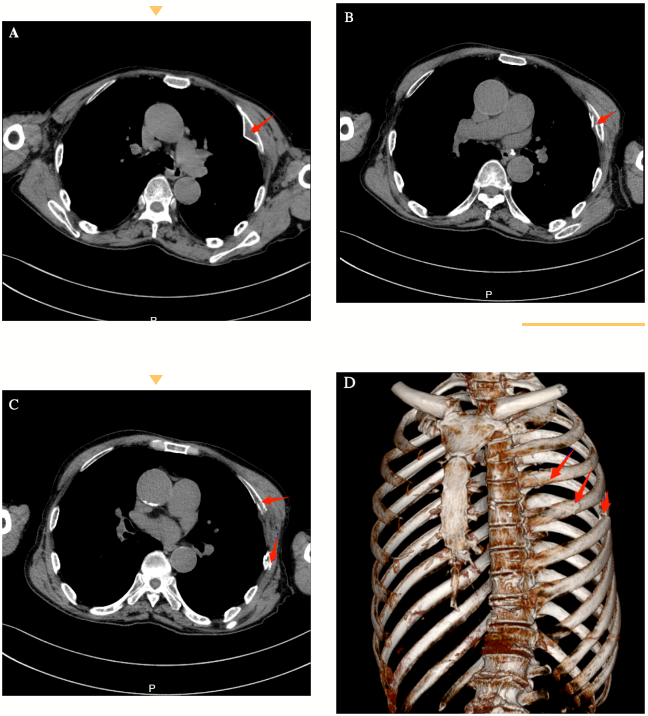

术前患者行肋骨CT+骨三维重建结果示:图A~D部分肋骨断端成粉碎状,断端锐利。